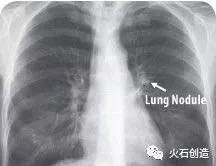

目前,传统检测方法仍无法发现肺部40毫米大小的结节,因此肺癌患者死亡率高达90%。惊喜的是,Enlitic开发的系统能发现小于5毫米的结节,使患者的生存率能增加10倍。

图中箭头所指为肺结节(Lung Nodule)